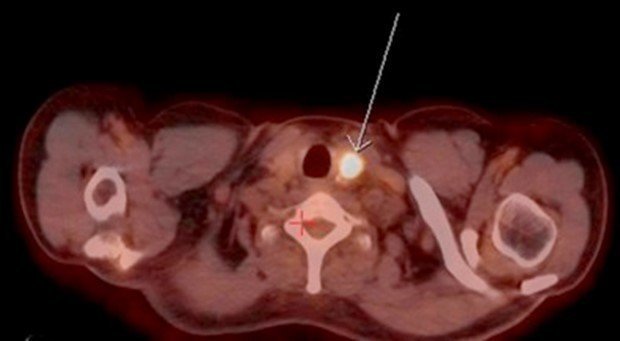

This simple test uses. Ultrasound is able to detect recurrent thyroid cancer when thyroglobulin levels are elevated but radioiodine or positron emission tomography scans fail to detect it. Kuo said it might also be a good idea to do an ultrasound scan of the thyroid at least once.

2 Parathyroid Ultrasound The. In 2013 I was diagnosed with Papillary Thyroid Cancer-Tall Cell Variant. This past January my Endo said that he believes that I may.